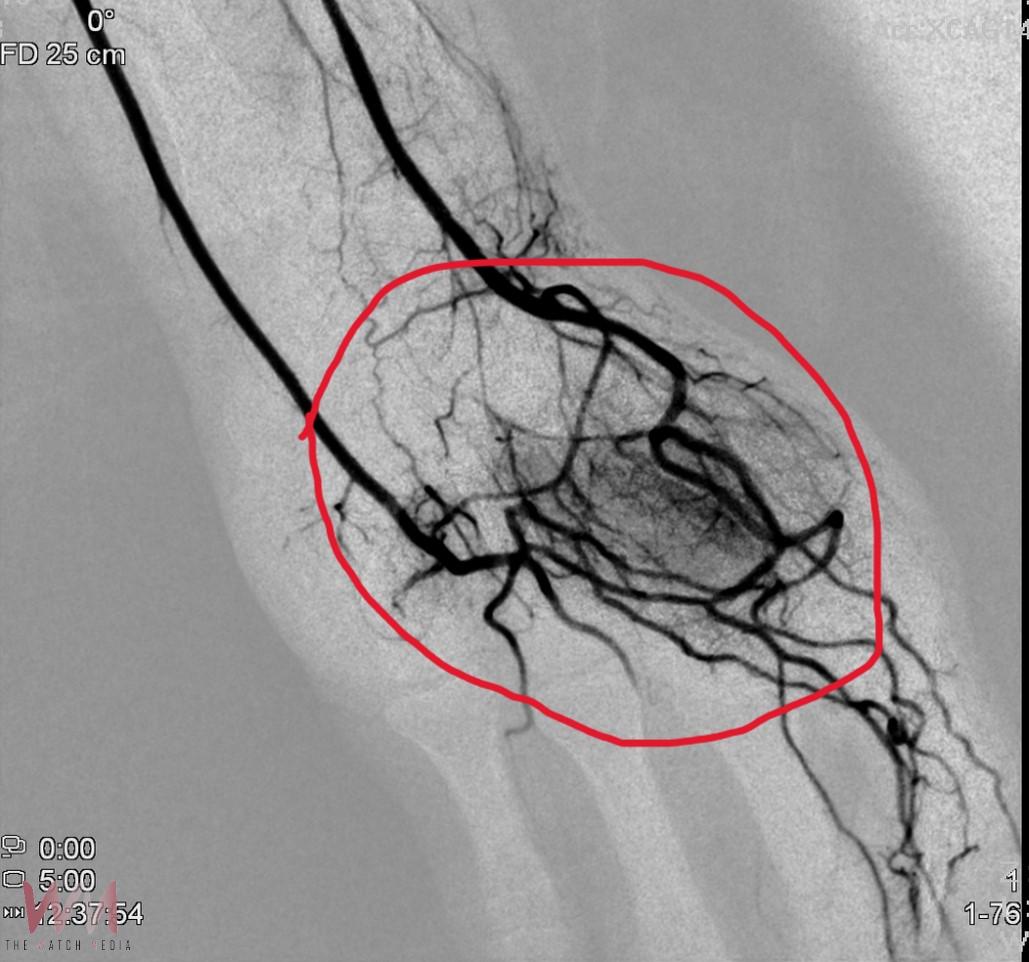

負責手術的林彤宥主任解釋,療程與心導管、腫瘤栓塞相似,從手腕橈動脈或鼠蹊部股動脈進行穿刺,在X光導引下將栓塞材料注入異常血管,使周邊神經因血流受阻而降低活性,疼痛訊號因而減少。「原本影像上呈現雲霧狀的血管,栓塞後馬上變得清晰許多,疼痛也跟著減輕。」林彤宥主任說。